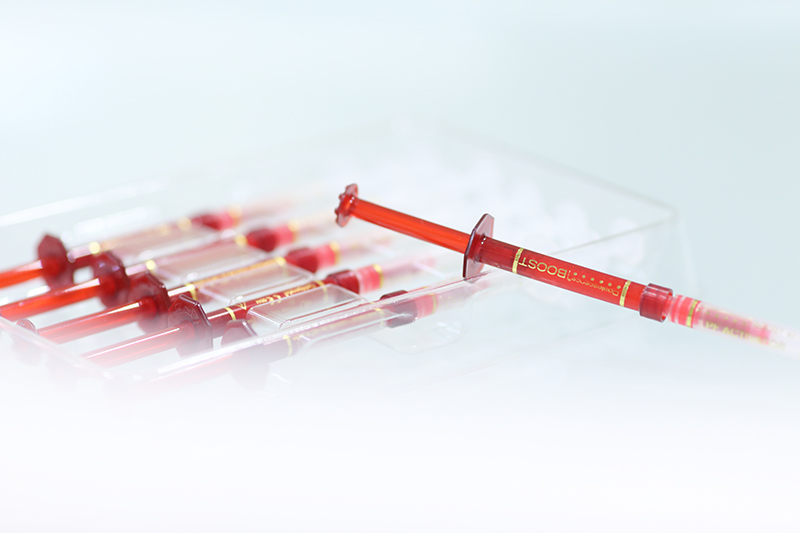

厚生労働省の認可を受けているホワイトニング剤は2~3種しかなかったのが最近、日本でもいろいろなメーカーから発売されるようになりました。当クリニックではポリリン酸を使ったものをはじめ、いろいろなメーカーのホワイトニング剤を研究し、より患者様1人ひとりの歯質に合わせたホワイトニング剤を選び、施術しております。

アメリカではすでに改良され、従来のものよりも歯を白くする効果が高く、知覚過敏を抑える成分が配合されるなど、品質や安全性がより高くなっています。

FDA(アメリカ食品医薬品局。日本の厚生労働省にあたる機関)の許可が下りたホワイトニング剤をいち早く使用し、より安全で快適なホワイトニング治療を行なっています。

ハーバード大学で使用しているホワイトニング剤も扱っております。

ホワイトニング剤を塗布します。

ホワイトニング剤を塗布します。